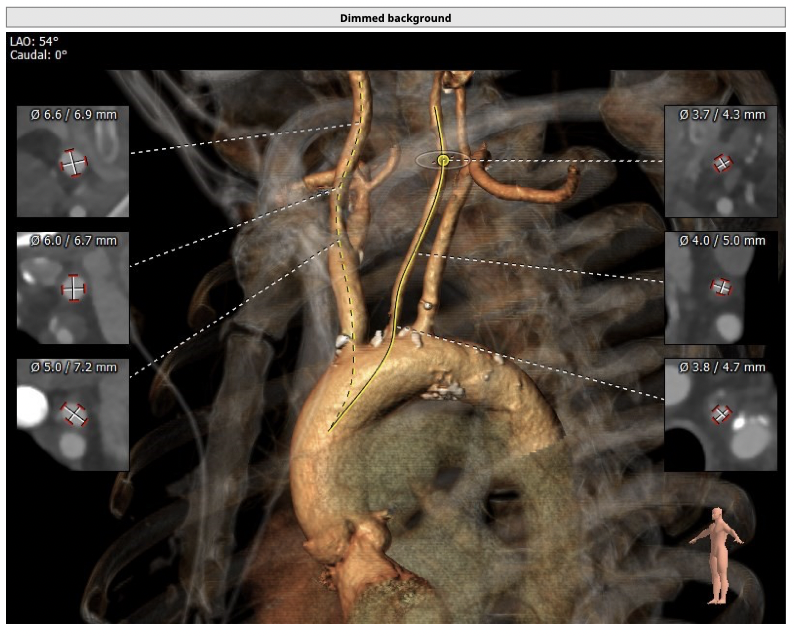

CT检查

①患者因规律透析导致钙磷代谢紊乱,外周血管斑块钙化严重,最狭窄处仅2.8mm,通路建立难度极大(左右颈动脉均不符合入路条件);

②主动脉根部钙化较轻,瓣叶肥厚,各交界缘不同程度粘连,瓣膜释放后具有瓣周漏风险;

③左冠高度不高,且瓣叶冗长,达冠脉开口层面,且冠脉存在狭窄,存在冠脉阻塞的风险;